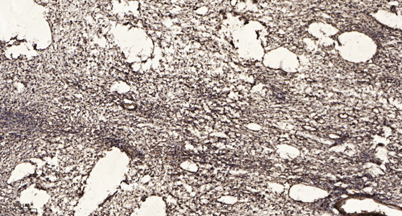

Product name: Sin3B rabbit pAb

Dilutions: WB 1:500-2000;IHC-p 1:50-300; ELISA 2000-20000